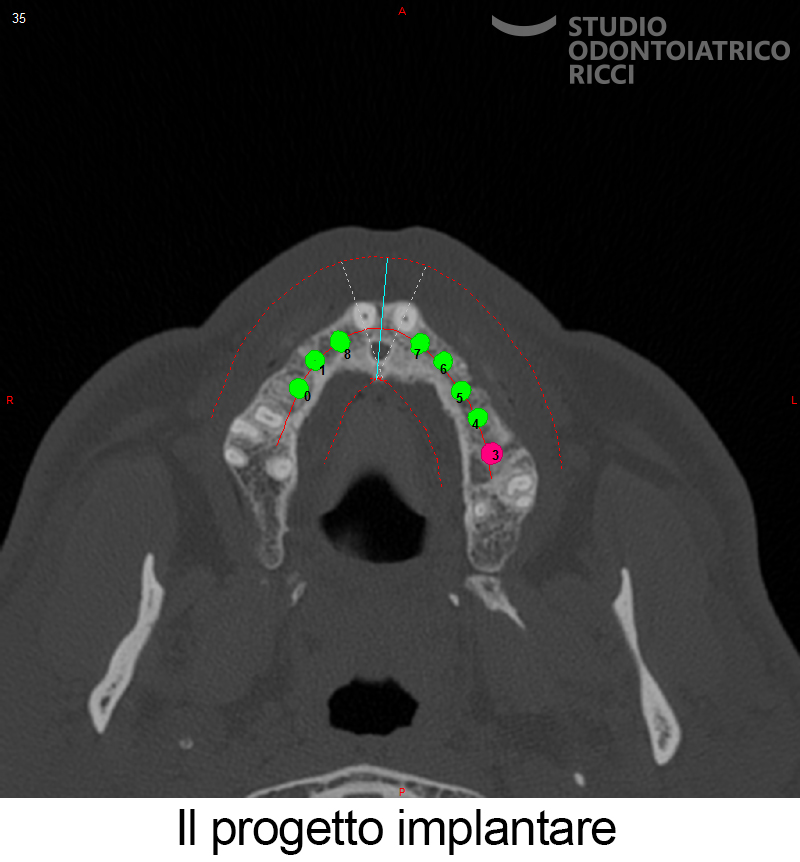

Dopo una fase di studio e pianificazione accurata, è possibile eseguire:

La maggior parte dei pazienti può sottoporsi a un trattamento implantare. È però fondamentale eseguire uno studio preliminare, con esami radiografici (es. TAC) per valutare:

quantità e qualità dell’osso